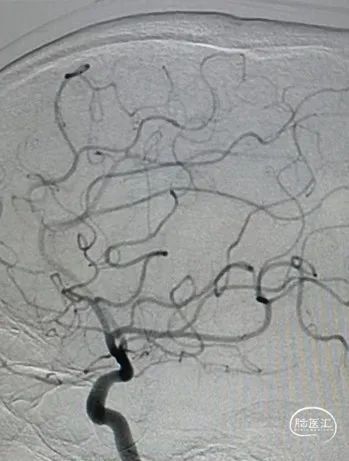

术后正位造影。

术后侧位造影